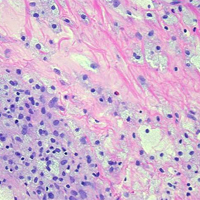

Ophthalmic PathologyImage

Richard J. Grostern, MD

Assistant Professor and Director, Section of Ophthalmic Pathology

Image

Richard J. Grostern, MD is fellowship trained in ocular pathology and oversee the department's clinical and educational pathology program. The resident laboratory experience takes place during the first year. Each first-year resident participates in two three-month rotations on the ophthalmic pathology service. Residents evaluate gross specimens and prepare them for fixation. Additionally, there are formalized one-on-one teaching with Dr. Grostern in the pathology lab. Although the volume of specimens derived from Rush patients is sufficient for the educational experience, additional unknown cases from the Ocular Pathology Library fortify the rotation. Dr. Grostern serve as ocular pathologist for the Cook County Medical Examiner. Emergency specimens can be processed and reviewed on virtually any day by the team. There is a one-hour block each month to conduct a pathology conference with the residents in morning didactic conferences.